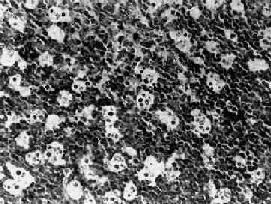

淋巴瘤細胞1、胃腸道原發性淋巴瘤的診斷標準1961年Dawson等提出了診斷胃腸道原發性淋巴瘤的5條標準:

實驗室檢查:組織病理學是確定診斷的可靠依據。